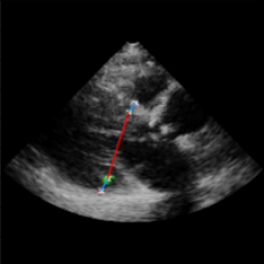

Left Ventricular Hypertrophy (LVH), one of the leading predictors of adverse cardiovascular outcomes, is the condition where heart’s mass abnormally increases secondary to anatomical changes in the Left Ventricle (LV) [10]. These anatomical changes include an increase in the septal and LV wall thickness, and the enlargement of the LV chamber. More specifically, Inter-Ventricular Septal (IVS), LV Posterior Wall (LVPW) and LV Internal Diameter (LVID) are assessed to investigate LVH and the risk of heart failure [21]. As shown in Figure 1 (a), four landmarks on a parasternal long axis (PLAX) echo frame can characterize IVS, LVPW and LVID, and allow cardiac function assessment. To automate this, machine learning-based (ML) landmark detection methods have gained traction.

It is difficult for such ML models to achieve high accuracy due to the sparsity of positive training signals (four or six) pertaining to the correct pixel locations. In an attempt to address this, previous works use 2D Gaussian distributions to smooth the ground truth landmarks of the LV [9, 13, 18]. However, as shown in Figure 1 (b), for LV landmark detection where landmarks are located at the wall boundaries (as illustrated by the dashed line), we argue that an isotropic Gaussian label smoothing approach confuses the model by being agnostic to the structural information of the echo frame and penalizing the model similarly whether the predictions are perpendicular or along the LV walls.